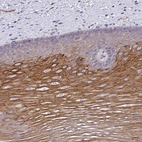

Immunohistochemical staining of human esophagus shows strong cytoplasmic positivity in squamous epithelial cells.